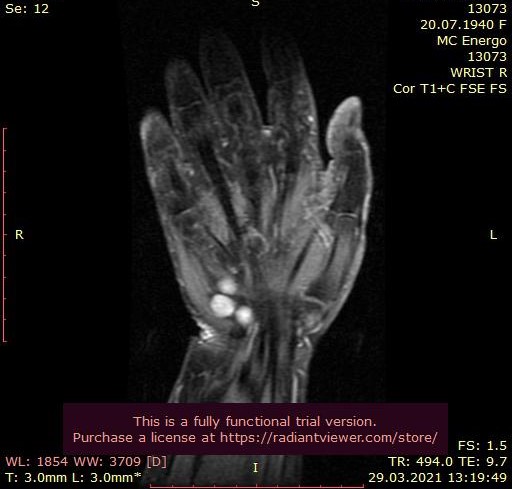

Специалисты Центра Алмазова приняли решение о госпитализации пациентки в стационар РНХИ им. проф. А. Л. Поленова. В ходе обследования медиками был выявлен редкий вид туннельной невропатии — сдавление локтевого нерва в канале Гюйона. Помимо этого, по данным УЗ-исследования выявлено образование канала Гюйона, природу которого можно было установить исключительно интраоперационно. Был поставлен точный диагноз «объемное образование локтевого нерва с выпадением функций правой кисти».

В результате оперативного вмешательства, выполненного на высочайшем уровне, утраченные функции полностью восстановились, была достигнута декомпрессия локтевого нерва с сохранением его целостности. Удалось установить доброкачественный характер образования, деформировавшего лучезапястный сустав, связочный аппарат ладонной поверхности правой кисти и сосудисто-нервные структуры, которое было удалено тотально.